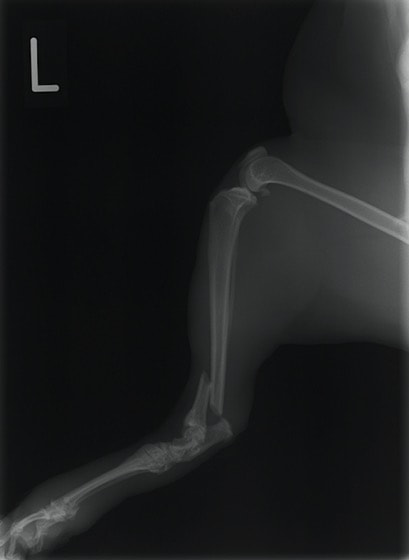

ペルシャ猫 11ヶ月齢 雄

他院にて左大腿骨遠位の成長板骨折(salter-harrisⅠ型)が認められており、治療相談を目的として来院。当院にて、キルシュナーワイヤーを用いたピンニングにより骨折部位の整復を行いました。術後の経過は良好で、現在も経過観察中です。

術前レントゲン